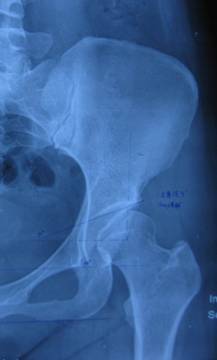

ce角:也称中心边缘角(如上图):指双侧股骨头中心点的连线的垂线与与